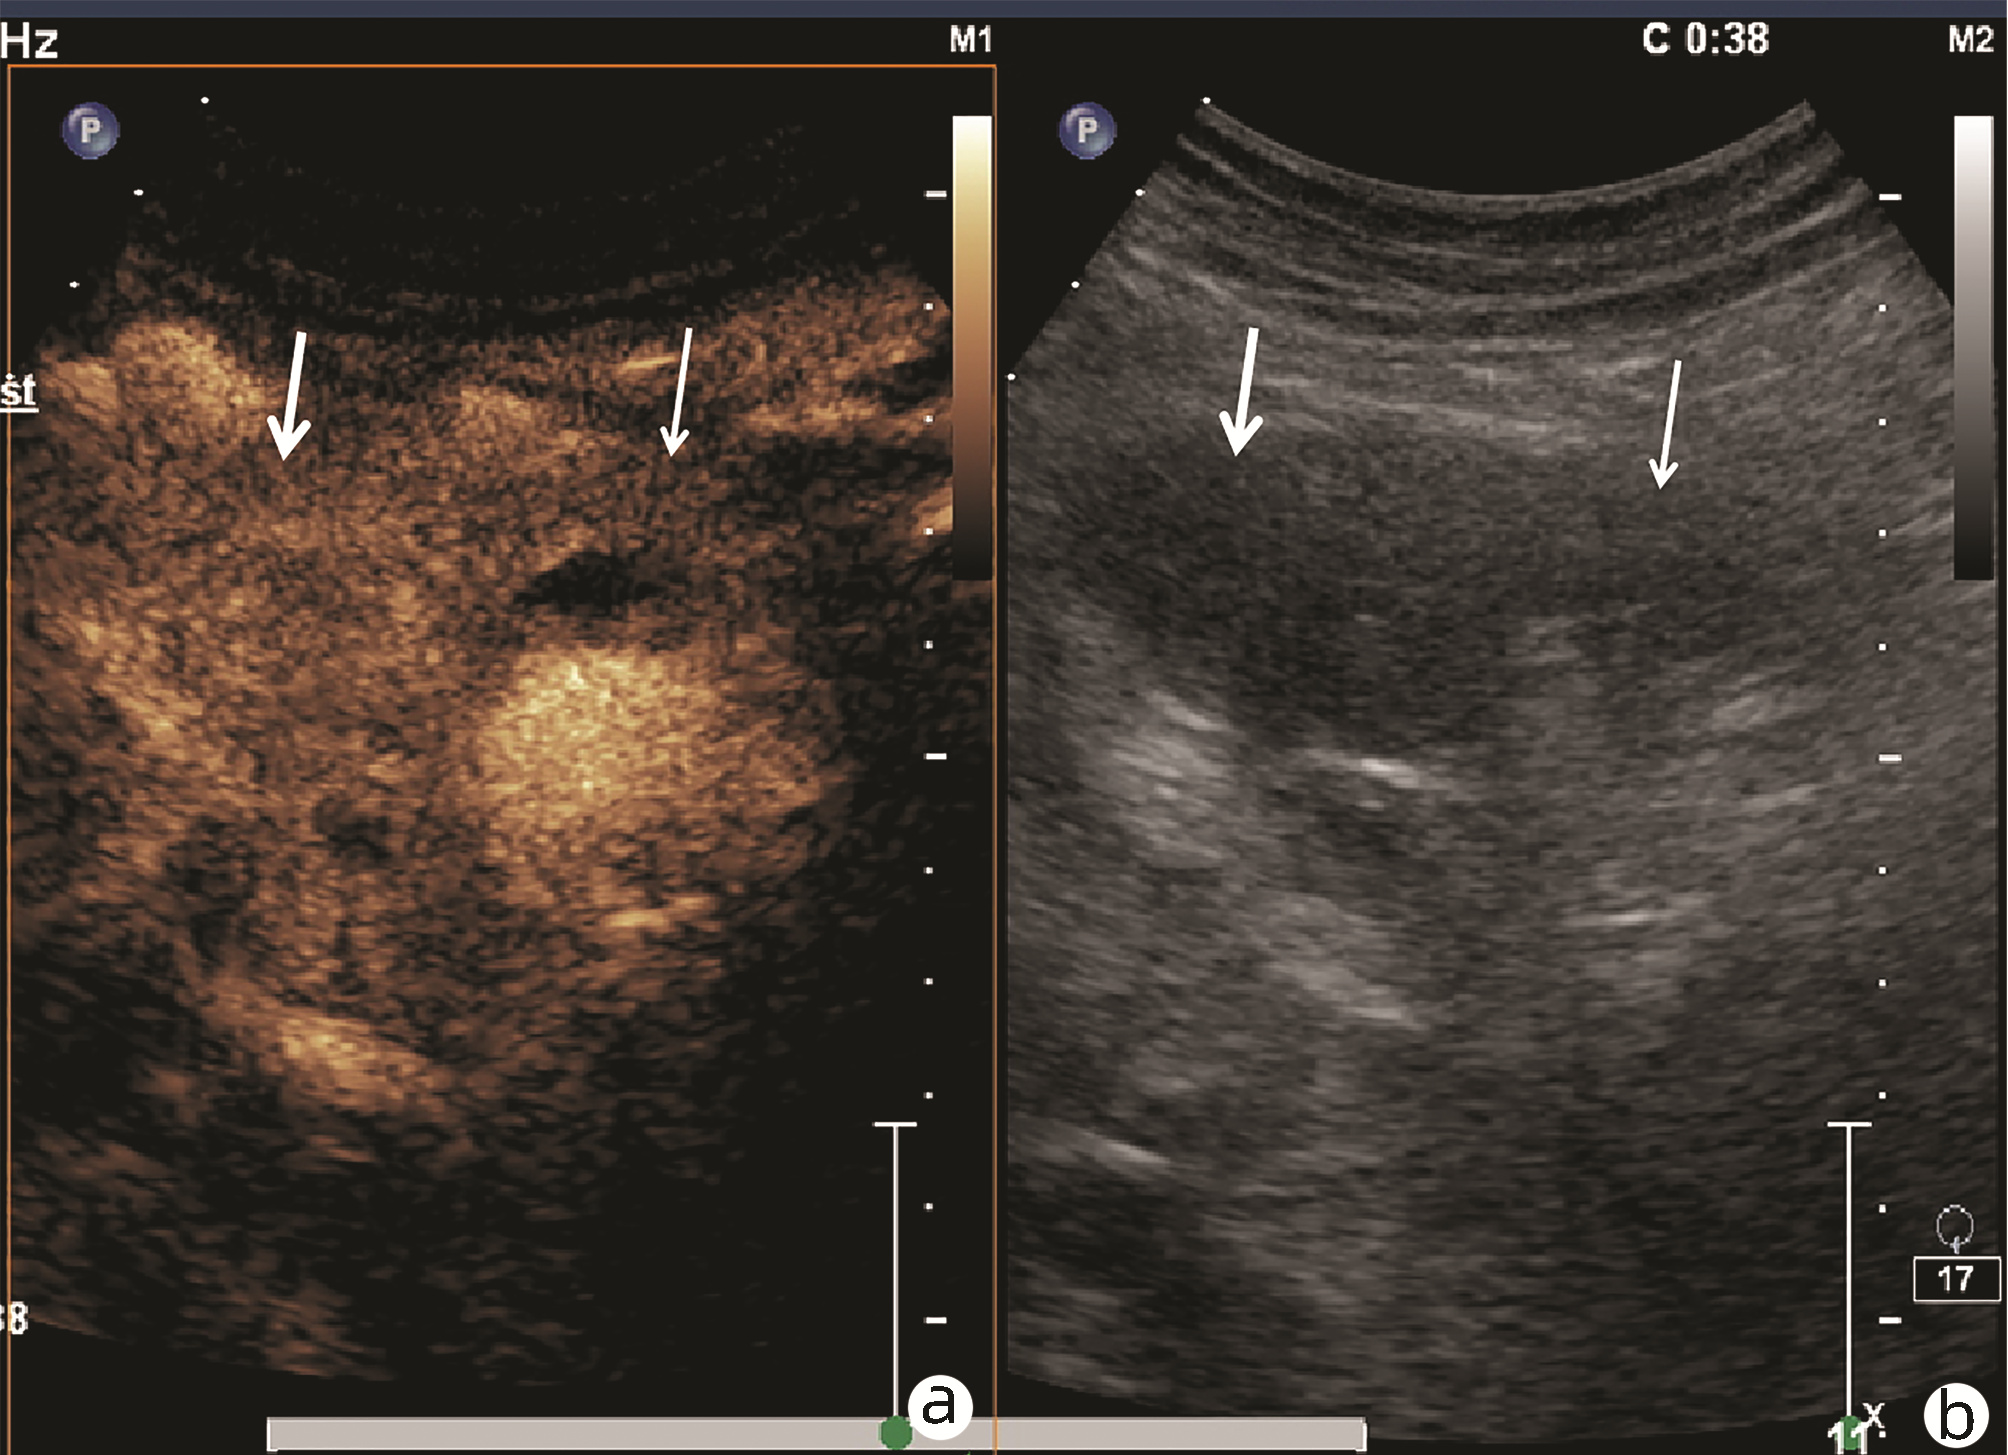

肿块型自身免疫性胰腺炎与胰腺导管腺癌的超声及超声造影表现分析

欧阳向柳, 韩云霞, 郑立春, 赵英春, 申新宇, 张文军, 王艳滨

2022, 38(6): 1351-1355. DOI: 10.3969/j.issn.1001-5256.2022.06.025

摘要(1431) HTML (553) PDF (3738KB)(51)

摘要:

目的  探讨超声及超声造影对肿块型自身免疫性胰腺炎(AIP)与胰腺导管腺癌(PDAC)的鉴别诊断价值。  方法  回顾性分析2015年1月—2020年12月唐山市工人医院确诊的11例肿块型AIP患者的临床资料及常规超声、超声造影资料,分析其特征性表现,并与23例PDAC患者的资料进行对比,计数资料两组间比较采用χ2检验。  结果  11例肿块型AIP超声造影的诊断准确性为63.64%,均为单发病灶,且均低回声,在边界清晰、形态规则、胰管扩张或截断、血流信号方面所占比例分别为54.55%、63.64%、18.18%、36.36%,而PDCA组分别为30.43%、34.78%、78.26%、21.74%,两组间是否伴胰管扩张或截断方面存在统计学差异(χ2=11.089,P<0.05),其余指标均无明显统计学差异(P值均>0.05)。超声造影中7例(63.64%)肿块型AIP动脉期呈高增强,4例(36.36%)呈等增强,静脉期5例(45.45%)呈高增强、6例(54.55%)呈等增强;23例PDAC中22例(95.65%)病灶在动脉期及静脉期均呈低增强,两者动、静脉期强化方式差异均有统计学意义(χ2值分别为30.345、30.084,P值均<0.05)。  结论  超声造影检查增强模式及是否伴胰管扩张或截断方面在肿块型AIP与PDCA的鉴别诊断中具有较高的价值。